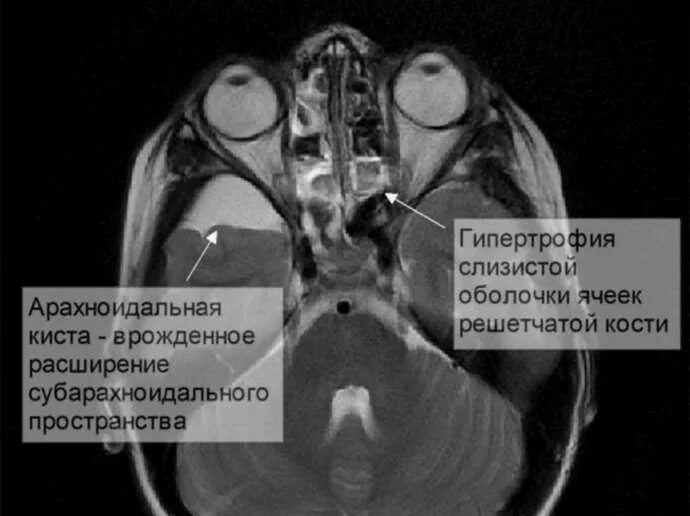

Неравномерное субарахноидальное пространство